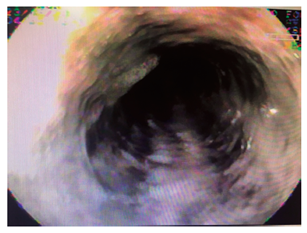

Mujer de 79 años, que consulta por urgencias por melanemesis y alteración de la conciencia. Como antecedente presentaba meningioma resecado, con síndrome convulsivo secundario, hipertensión arterial no controlada y enfermedad pulmonar obstructiva crónica. En los exámenes presentaba leucocitosis con neutrofilia (89 %); creatinina de 1,84 mg/dL, hipocloremia (92 mEq/L) e hiponatremia (129 mEq/L). La endoscopia mostró esfacelo del epitelio esofágico en los dos tercios inferiores y sangrado difuso en la capa (Figuras 1, 2, 3 y 4), sin cambios en el calibre. Se desconoce su evolución y su desenlace.